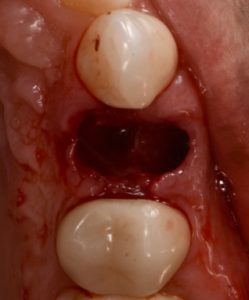

This video demonstrates alveolar ridge preservation following atraumatic surgical extraction of an endodontically treated tooth. Emphasis is placed on minimizing surgical trauma to preserve existing hard and soft tissues.

The case features flap management in the presence of a buccal dehiscence, followed by bone graft placement and stabilization using a dense polytetrafluoroethylene (d-PTFE) membrane. Surgical principles, membrane selection, and handling techniques are discussed to optimize ridge dimensions and facilitate future implant placement.

- Flap design considerations in sites with buccal dehiscence